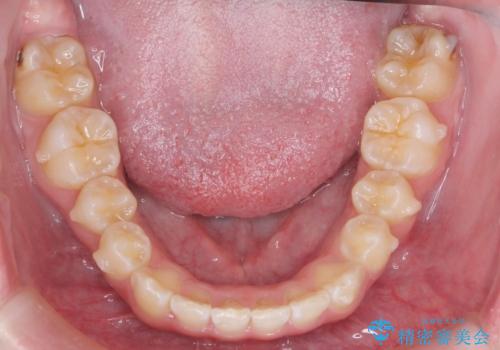

前歯の並び インビザライン 非抜歯で 深いかみ合わせの治療

- 前歯の並びを気にして来院。

上の前歯が内側に倒れこんでいました。

インビザラインで前歯の並びを整えています。

前歯の重なりが大きいいわゆる過蓋咬合を呈していましたが、ある程度適正な重なりにすることができました。